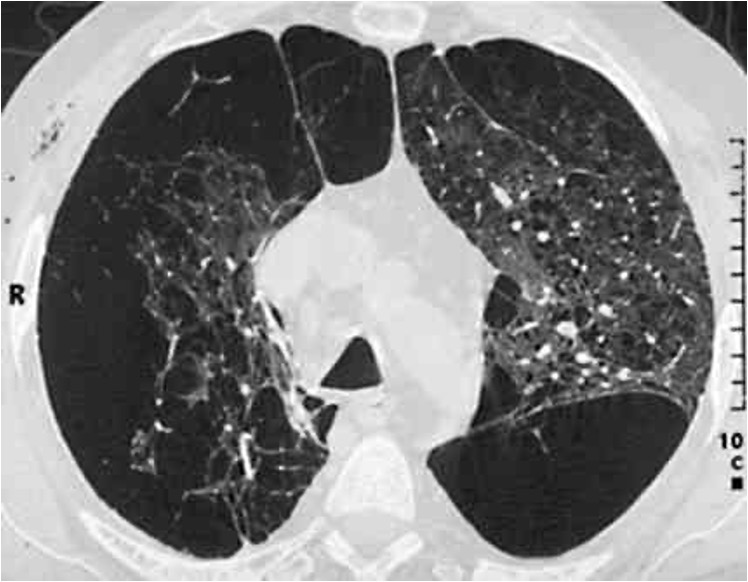

Die chronisch obstruktive Lungenerkrankung (COPD) ist wie oben bereits ausgeführt eine häufige, aber verhinderbare und fortschreitende chronische Atemwegserkrankung, die durch eine chronische Entzündung charakterisiert ist. Diese wird zu 90 Prozent durch Rauchen verursacht und infolgedessen kommt es zur nicht-reversiblen Atemwegsobstruktion mit den Symptomen Husten, Luftnot und Hypoxie. Bei dieser Erkrankung kommt es vor allem beim fortgesetzten Zigarettenrauchen zum Fortschreiten irreparabler Einschränkungen der Lungenstruktur und der Lungenfunktion. Durch diese irreparable Zerstörung der Alveolen kommt es zur Ausbildung eines Lungenemphysems mit Überblähung (unter normobaren Bedingungen, das heißt über Wasser) und dadurch zur Abnahme der Elastizität der Lunge (Abb. 2).

Abb. 2: Computertomographie-Aufnahme des Brustkorbs

(CT-Thorax), Transversalebene (axialer Schnitt).

Ausgedehntes Lungenemphysem mit multiplen

Emphysembullae (große Blase rechts unten sowie mehrere Blasen links oben und links unten im

Bild). Diese Emphysemblasen stellen eine lebensbedrohliche Kontraindikation zur Ausübung des

Tauchsports, aber auch für das Schnorcheltauchen dar, da stets die Gefahr der Ruptur und somit

die Entstehung eines Pneumothorax (Lungenriss) sowohl in der Kompressions-, als auch in der

Dekompressionsphase besteht. © Dr. Dr. Philipp Stahl

Aufgrund des hier Ausgeführten schließt das Vorhandensein eines Lungenemphysems bei COPD-Patientinnen und -Patienten eine Tauchtauglichkeit aus. Weiterhin besteht bei jeglichem Grad der Einschränkung der Lungenfunktion, das heißt bei bestehender Atemwegsobstruktion aufgrund der beschriebenen fehlenden Reversibilität der Atemwegsverengung, eine absolute Kontraindikation gegenüber der Ausübung des Tauchsports. Zusammenfassend lässt sich zur Tauchtauglichkeit bei COPD festhalten, dass nur das Krankheitsbild einer chronischen Bronchitis, die mit Husten und Schleimproduktion einhergeht, allerdings ohne Einschränkung der Lungenfunktion mit dem Tauchen vereinbar ist. Die chronische Bronchitis kann gewissermaßen als Vorstufe der COPD gesehen werden. Der konsequente Rauchverzicht kann ein Fortschreiten der Erkrankung zur COPD gegebenenfalls verhindern.